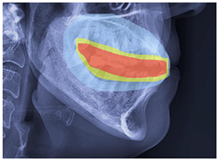

2.3. ROI Identification, YOLO-UNet-Based

3. Results